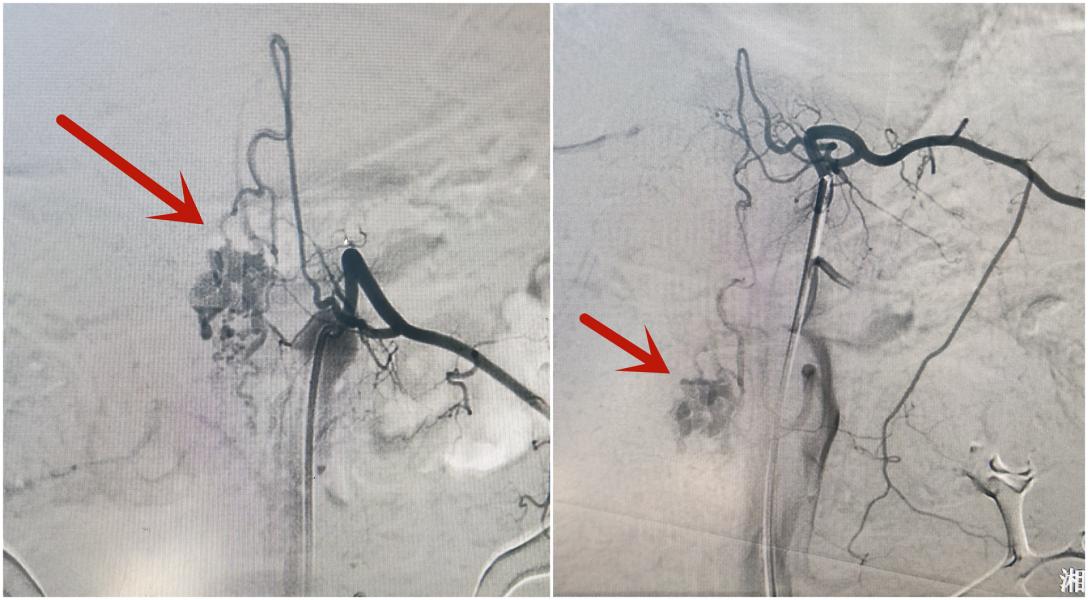

术中造影情况,红色箭头为病变

术中操作情况       经过术前仔细评估患者病情和全身情况,神经外二科团队在DSA室的大力支持和配合下,局麻下定位、穿刺、置鞘、超选造影,术毕拔管、拔鞘、加压包扎......台上术者们屏神静气、配合默契,历时3小时顺利完成全脊髓血管造影,造影证实患者系胸腰段硬脊膜下髓周动静脉瘘(II型)。整个过程一气呵成,患者全程清醒,术后病情平稳。

髓周动静脉瘘(PMAVFs)是一种罕见的脊髓血管病变,患者可产生脊髓压迫症状,病程进展7至9年可能出现截瘫,该病的治疗主要通过血管内栓塞介入治疗或手术治疗来改善病情。经神经外二科全科讨论,下一步将在完善术前准备后对患者行血管内栓塞介入治疗。